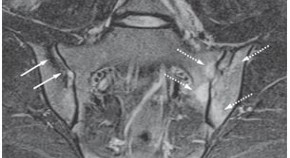

• In the second of two Perspectives articles regarding the use of MRI to detect inflammatory lesions in early preclinical axial spondyloarthritis, van der Heijde et al. defend the inclusion of MRI sacroiliitis in the 2009 ASAS classification criteria and acknowledge the importance of expert opinion in the diagnosis of this disease.